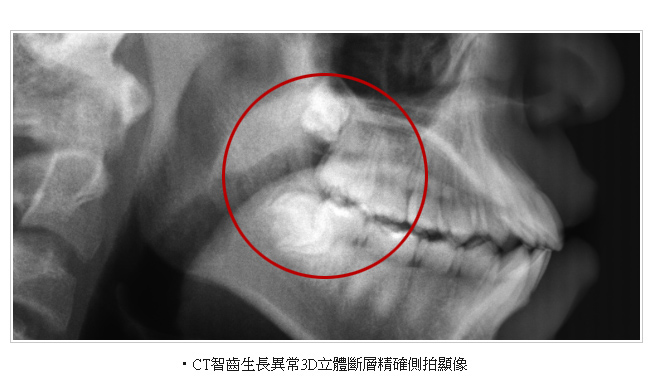

牙科專用的電腦斷層(Computed Tomography 簡稱CT)和一般的醫療電腦斷層的不同在於傳統牙科X光攝影所得的平面影像受到組織重疊的影響,無法觀察到內部的實際狀況,醫師常常因此造成誤判,為解決此問題,就需要牙科專用的3D電腦斷層攝影;若與傳統醫療電腦斷層相比較,牙科3D電腦斷層攝影有很多優點,如輻射劑量只有一般電腦斷層的1/50;採站姿或坐姿攝影,方便行動不便的患者;切片厚度一般醫療電腦斷層是 2.0 公厘,牙科3D電腦斷層則只有0.1公厘,解析度之高,比起一般醫療電腦斷層,影像當然來得細緻和精確。

電腦斷層掃描合成3D影像,術前準確模擬植牙角度及位置。